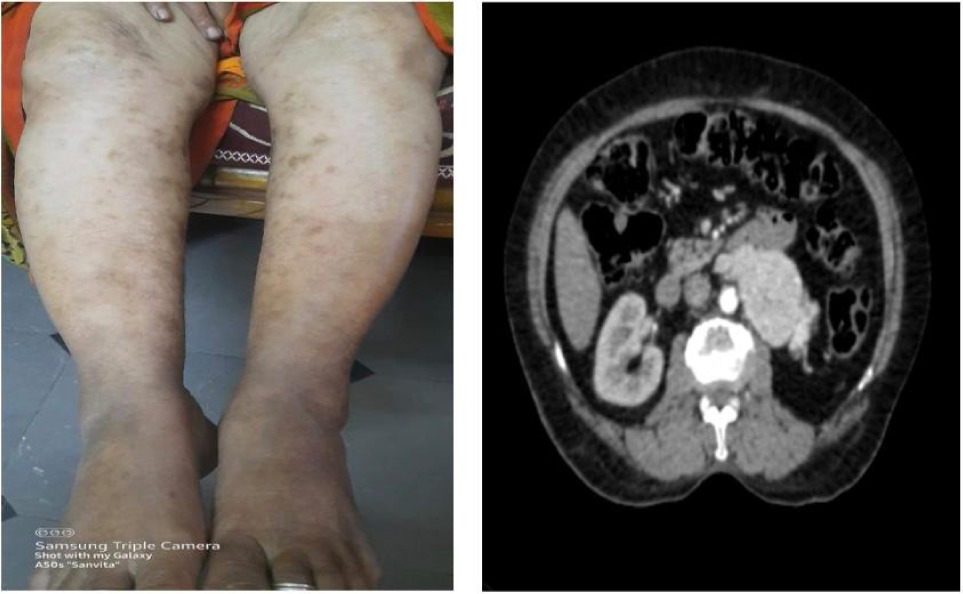

On examination, multiple erythematous, palpable, nonblanching purpuric lesions were observed on both lower limbs (Figure 1). The lesions were of irregular shapes and varied in size. Some of the lesions had vesicles over them. These lesions were most prominent on the ankles and gradually extended up to the knees. The lesions were slightly tender to palpation but no significant warmth or erythema was noted around the lesions. The patient also had a scar over the left lumbar region, which was nontender, consistent with prior nephrectomy. Abdominal examination revealed a nontender, retroperitoneal mass approximately 10 × 8 cm in size in the left lower quadrant. The mass was firm to hard and had an ovoid shape with ill-defined borders. Systemic and pelvic examinations were unremarkable, and there were no signs of lymphadenopathy or organomegaly.

Figure 1: Erythematous palpable nonblanchable purpuric lesions with vesicles.

A contrast-enhanced CT urogram was then performed, which revealed a heterogeneously enhancing left retroperitoneal mass with necrotic areas. The mass had extended into the periaortic region and involved the IVC, suggestive of recurrent RCC with possible vascular invasion (Figure 2).

Figure 2: Contrast CT showing heterogeneously enhancing mass in the left retroperitoneum with intrinsic foci of necrotic areas with involvement of periaortic lesion and extension into the inferior vena cava.